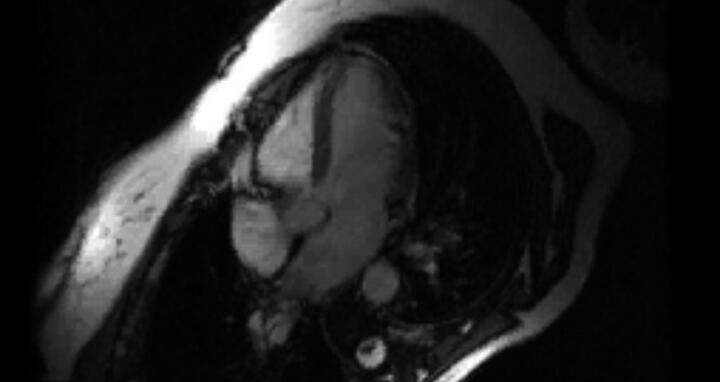

… und ein krankes Herz, das vergrößert ist. Abb.: J. Fielitz/​MDC